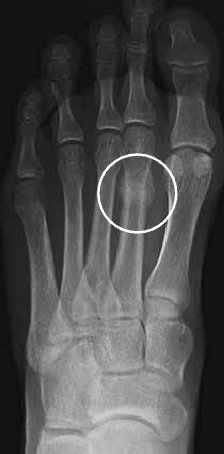

Figure skating is one of the most demanding sports, both physically and mentally. We see figure skaters as graceful and elegant when we watch them float across the ice, but this grace and elegance involves many hours of practice, both on and off the ice, before they can deliver a superior performance. Falls and repetitive movements often result in injuries. The most common injuries include Achilles tendinitis, tendinitis of the lower limbs, patellofemoral syndrome, sacroiliac pain and stress fractures.

“The muskoskeletal system must obviously be at its best for the body to performthese high-flying jumps, due to the explosive movements needed for the upward propulsion of the skaters, in order to potentially succeed in competition.Calves, Achilles tendons and knees are put under great pressure, both during thrust and landing” according to Dr. Lepage, chiropractor.